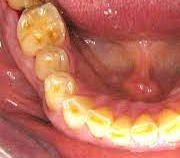

歯は酸で溶かされ虫歯になります。

虫歯予防は、結局は歯を溶かす「酸」との戦いでした。

虫歯原因菌が歯につき、砂糖から乳酸を産生して歯を溶かすということでした(germ theory)。

歯を取り巻く環境が歯を溶かす「酸性」になるには、砂糖と虫歯菌だけでは役不足です。

宿主側の体内環境が酸性に傾くと、歯は溶けます。唾液など分泌液で菌が出す乳酸も中和ができません。

よって、う蝕円錐という、内部で虫歯が広がる(象牙芽細胞突起の末端から乳酸に侵される)という特徴が出ます。

咬頭部や切端部の脱灰も起こり得ます。